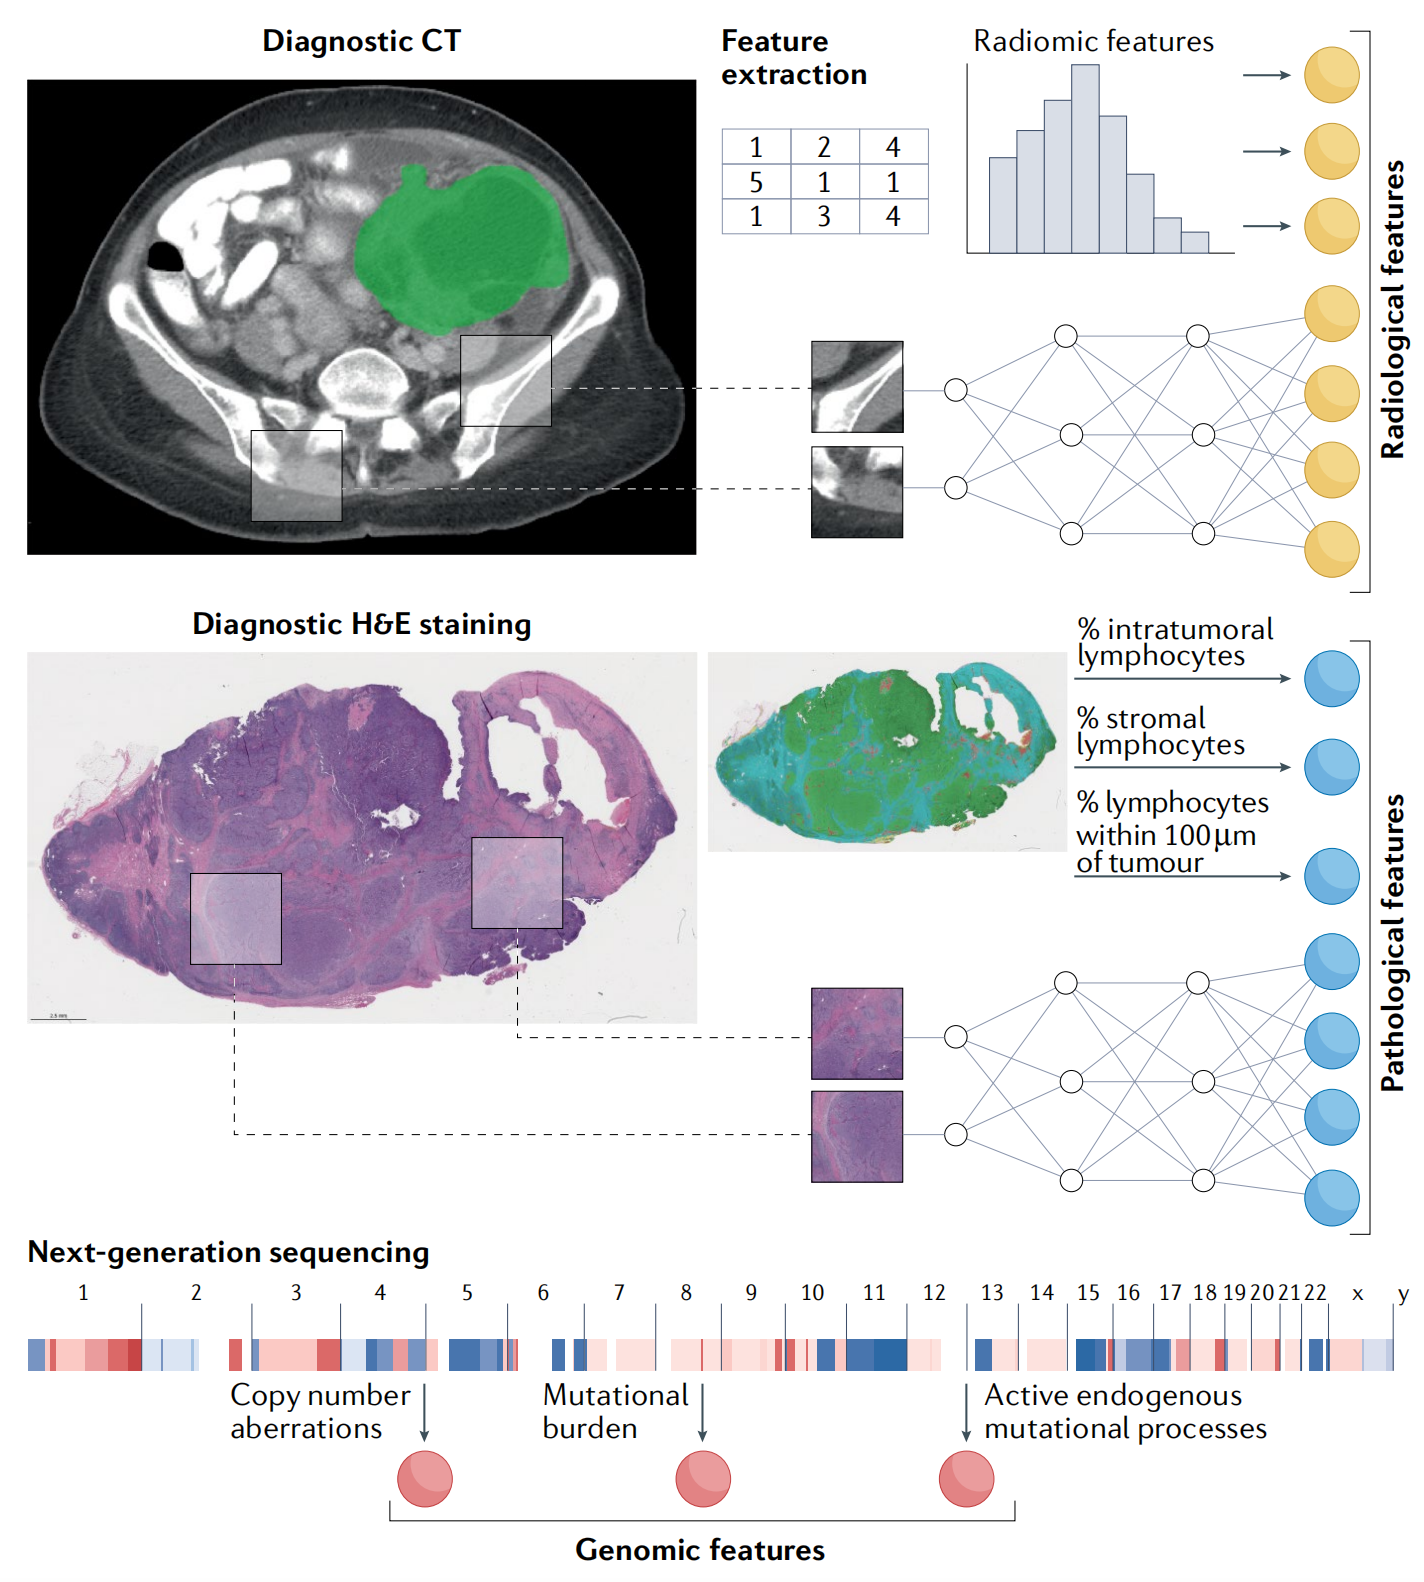

图 1 展示了用于整合的示例数据模态,包括放射学、组织病理学和基因组学信息。这个图表以视觉方式呈现了如何从不同数据源中提取特征,并将其用于构建一个综合的、多模态的数据集,以便于进行精准肿瘤学研究。

以下是对这些数据模态的解释:

-

放射学(Radiology):

- 放射学图像(如CT扫描、MRI、PET扫描)提供了关于肿瘤位置、大小和形态的视觉信息。

- 通过放射组学(radiomics)技术,可以从这些图像中自动提取定量特征,如肿瘤的密度、形状和纹理特征。

-

组织病理学(Histopathology):

- 组织病理学涉及对组织样本的细胞和组织结构进行显微镜检查。

- 通过数字化染色玻片(如H&E染色),可以进行图像分析,以识别肿瘤细胞的形态特征、组织结构和肿瘤-免疫系统界面。

-

基因组学(Genomics):

- 基因组学数据包括肿瘤组织的基因组测序结果,可以揭示遗传变异、突变负荷、拷贝数变异等信息。

- 这些数据有助于了解肿瘤的分子特征,预测对特定治疗的敏感性和耐药性。

通过深度学习或其他机器学习技术,可以从每种模态中提取特征,并将这些特征用于训练模型,以预测临床结果或发现新的生物标志物。

整合这些不同模态的数据对于精准肿瘤学至关重要,因为它允许医生和研究人员更全面地了解肿瘤的生物学特性,并为每个患者定制更有效的治疗策略。通过分析这些多模态数据,研究人员可以发现不同数据类型之间的关联,从而更好地预测治疗反应和疾病进展。